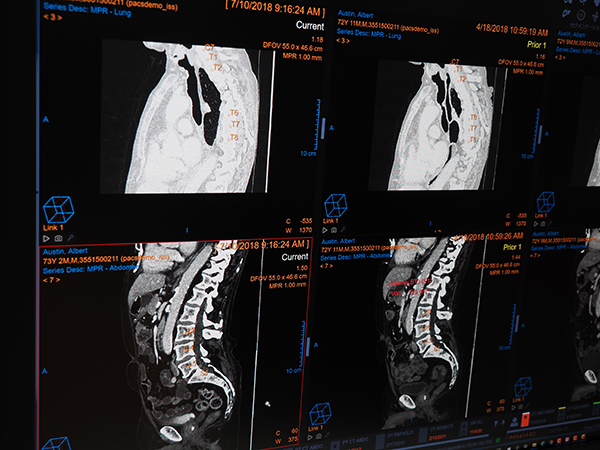

ケアストリームヘルスのVue PACS Clientは,ボリュームデータをベースにした3D自動位置合わせ機能(複数検査間のスライス位置の同期)や病変セグメンテーション(病変領域の抽出,計測,経時変化の自動フォローアップ,RECISTに対応した自動計算)などの機能を特徴とする。これらの機能は,今でこそ同様の機能が他社システムでも搭載されているが,Vue PACSの登場当初から実現されており,先進機能をいち早く製品化する同社の技術力の高さを感じさせる。ブースでは,基本機能として自動位置合わせ(レジストレーション)のほか,マウスの右クリック左クリックからの操作,キーボードショートカットによる操作,また任意の機能のショートカットへの登録など,読影業務をサポートする機能を改めて紹介した。また,新しく搭載された機能としてチャットと画面共有を活用した読影支援について説明した。これは,検査や画像についてアドバイスやコメントがほしいときに,ネットワーク上でSNSのような機能を利用して気軽に会話ができる“チャット機能”と,画面を共有して互いに同じ画像を参照できる“画面共有”で構成される。画面共有では,画像の拡大,ウィンドウレベルの変更,アノテーションなどで,その場にいるようなディスカッションが可能なことを端末を使って紹介した。

同じく自社開発の脊椎ラベリングの自動化機能(W.I.P.)